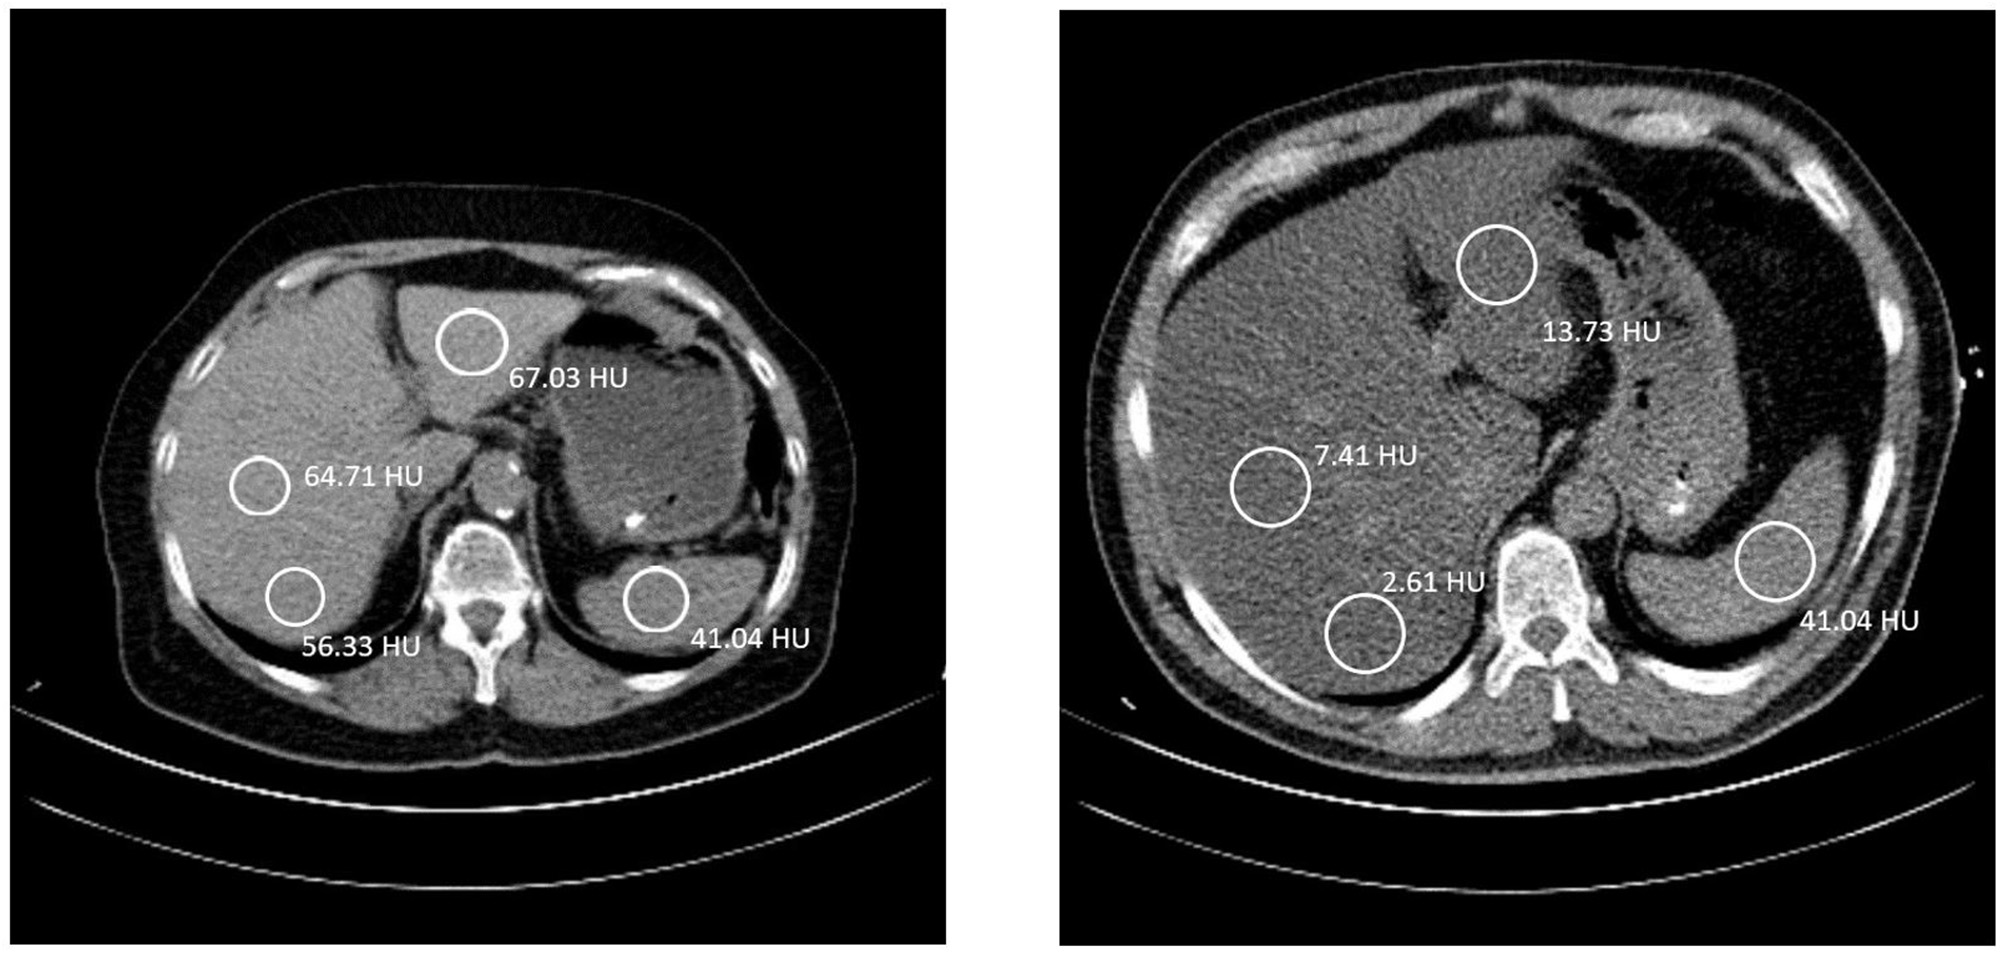

For each patient, Hounsfield unit (HU) values of four different regions of interest (ROIs) were measured according to Kerut et al. (8), one in the spleen and three in the liver. The spherical ROIs of the liver were spread out, one in the posterior part of the right lobe, one in the anterior part of the right lobe, and one in the left lobe (Figure 1). All ROIs were over 100 mm2 in size, and vasculature, cysts, and other heterogeneous areas were avoided. Measurements of HU values of selected ROIs were performed using IDS7 PACS (Sectra AB IDS7, 2019, version 21.1). The calculation of the liver to spleen ratio (L/S) was done by taking an average HU value of the two ROIs in the right lobe of the liver and dividing this value by the HU of the spleen, for example, L/S = [(49.3 + 51.3)/2]/43.9 = 1.15 (mean values from our results). The criterion for NAFLD was L/S < 1 based on average L/S of CT scan 1 and 2.

Figure 1

Left: A 70-year-old female, with liver to spleen ratio (L/S) of 1.15. The coloration of the liver is clearly brighter than the spleen. She has a BMI of 26.0 kg/m2 and has been diagnosed with hypertension, dyslipidemia, and a previous myocardial infarction. Right: A 50-year-old male, with L/S ratio of 0.12. The liver has a much darker color than the spleen, indicating a fatty liver. He has a BMI of 30.0 kg/m2 and has been diagnosed with type II diabetes mellitus, hypertension, and dyslipidemia. The patient also has less subcutaneous fat and more visceral fat. In both images the table is 40 cm wide. A good indication of the size difference between the two patients.